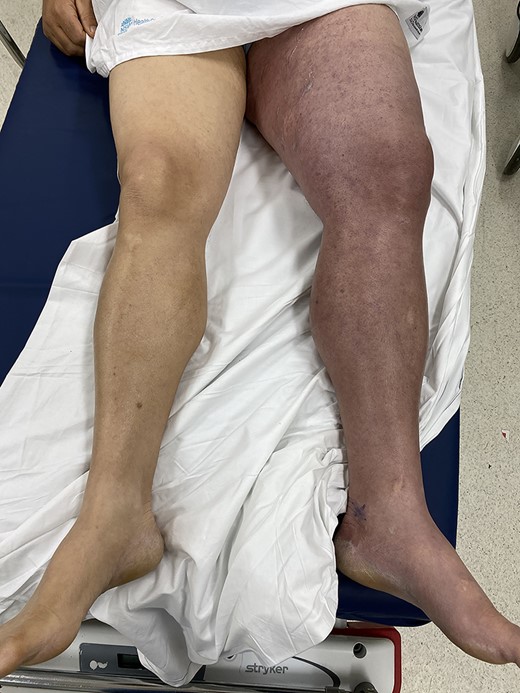

A 56-year-old man presented to the emergency department with acute left leg swelling, discolouration and pain. He had undergone a cardiac ablation procedure for atrial arrhythmia via a bilateral femoral vein approach ~2 weeks prior. His other significant medical comorbidities included hypertension, diabetes, renal calculi, supraventricular tachycardia (SVT), hypercholesterolaemia, obesity, suspected obstructive sleep apnoea and depression. He worked as a hospital cleaner. On examination, his left leg was grossly swollen from the hip down, with tense compartments. His leg illustrated a purple discolouration (Fig. 1), and his foot was cool to touch with a capillary refill of ~2–3 seconds. His femoral pulse and posterior tibial pulses were palpable. Motor function and sensation in the lower limb were both preserved.

Patient presents with a grossly swollen and discoloured left leg.